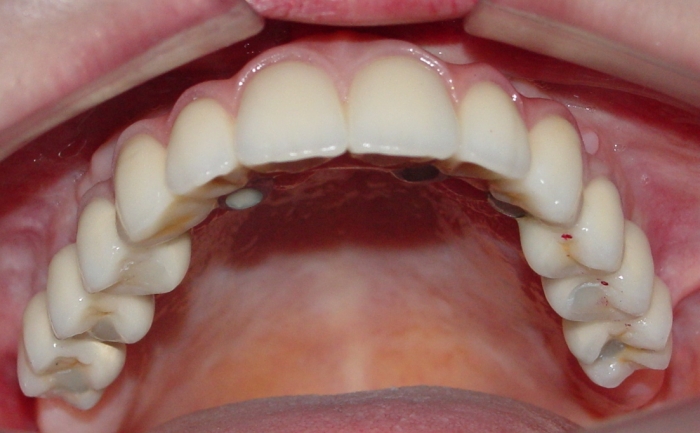

Imagem inicial